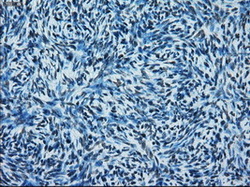

- Immunohistochemical staining of paraffin-embedded prostate tissue using anti-ERCC1 mouse monoclonal antibody. (Dilution 1:50).

- Submitted by

- LSBio (provider)

- Enhanced method

- Genetic validation

- Main image

- Experimental details

- Immunohistochemical staining of paraffin-embedded Carcinoma of prostate tissue using anti-ERCC1 mouse monoclonal antibody. (Dilution 1:50).